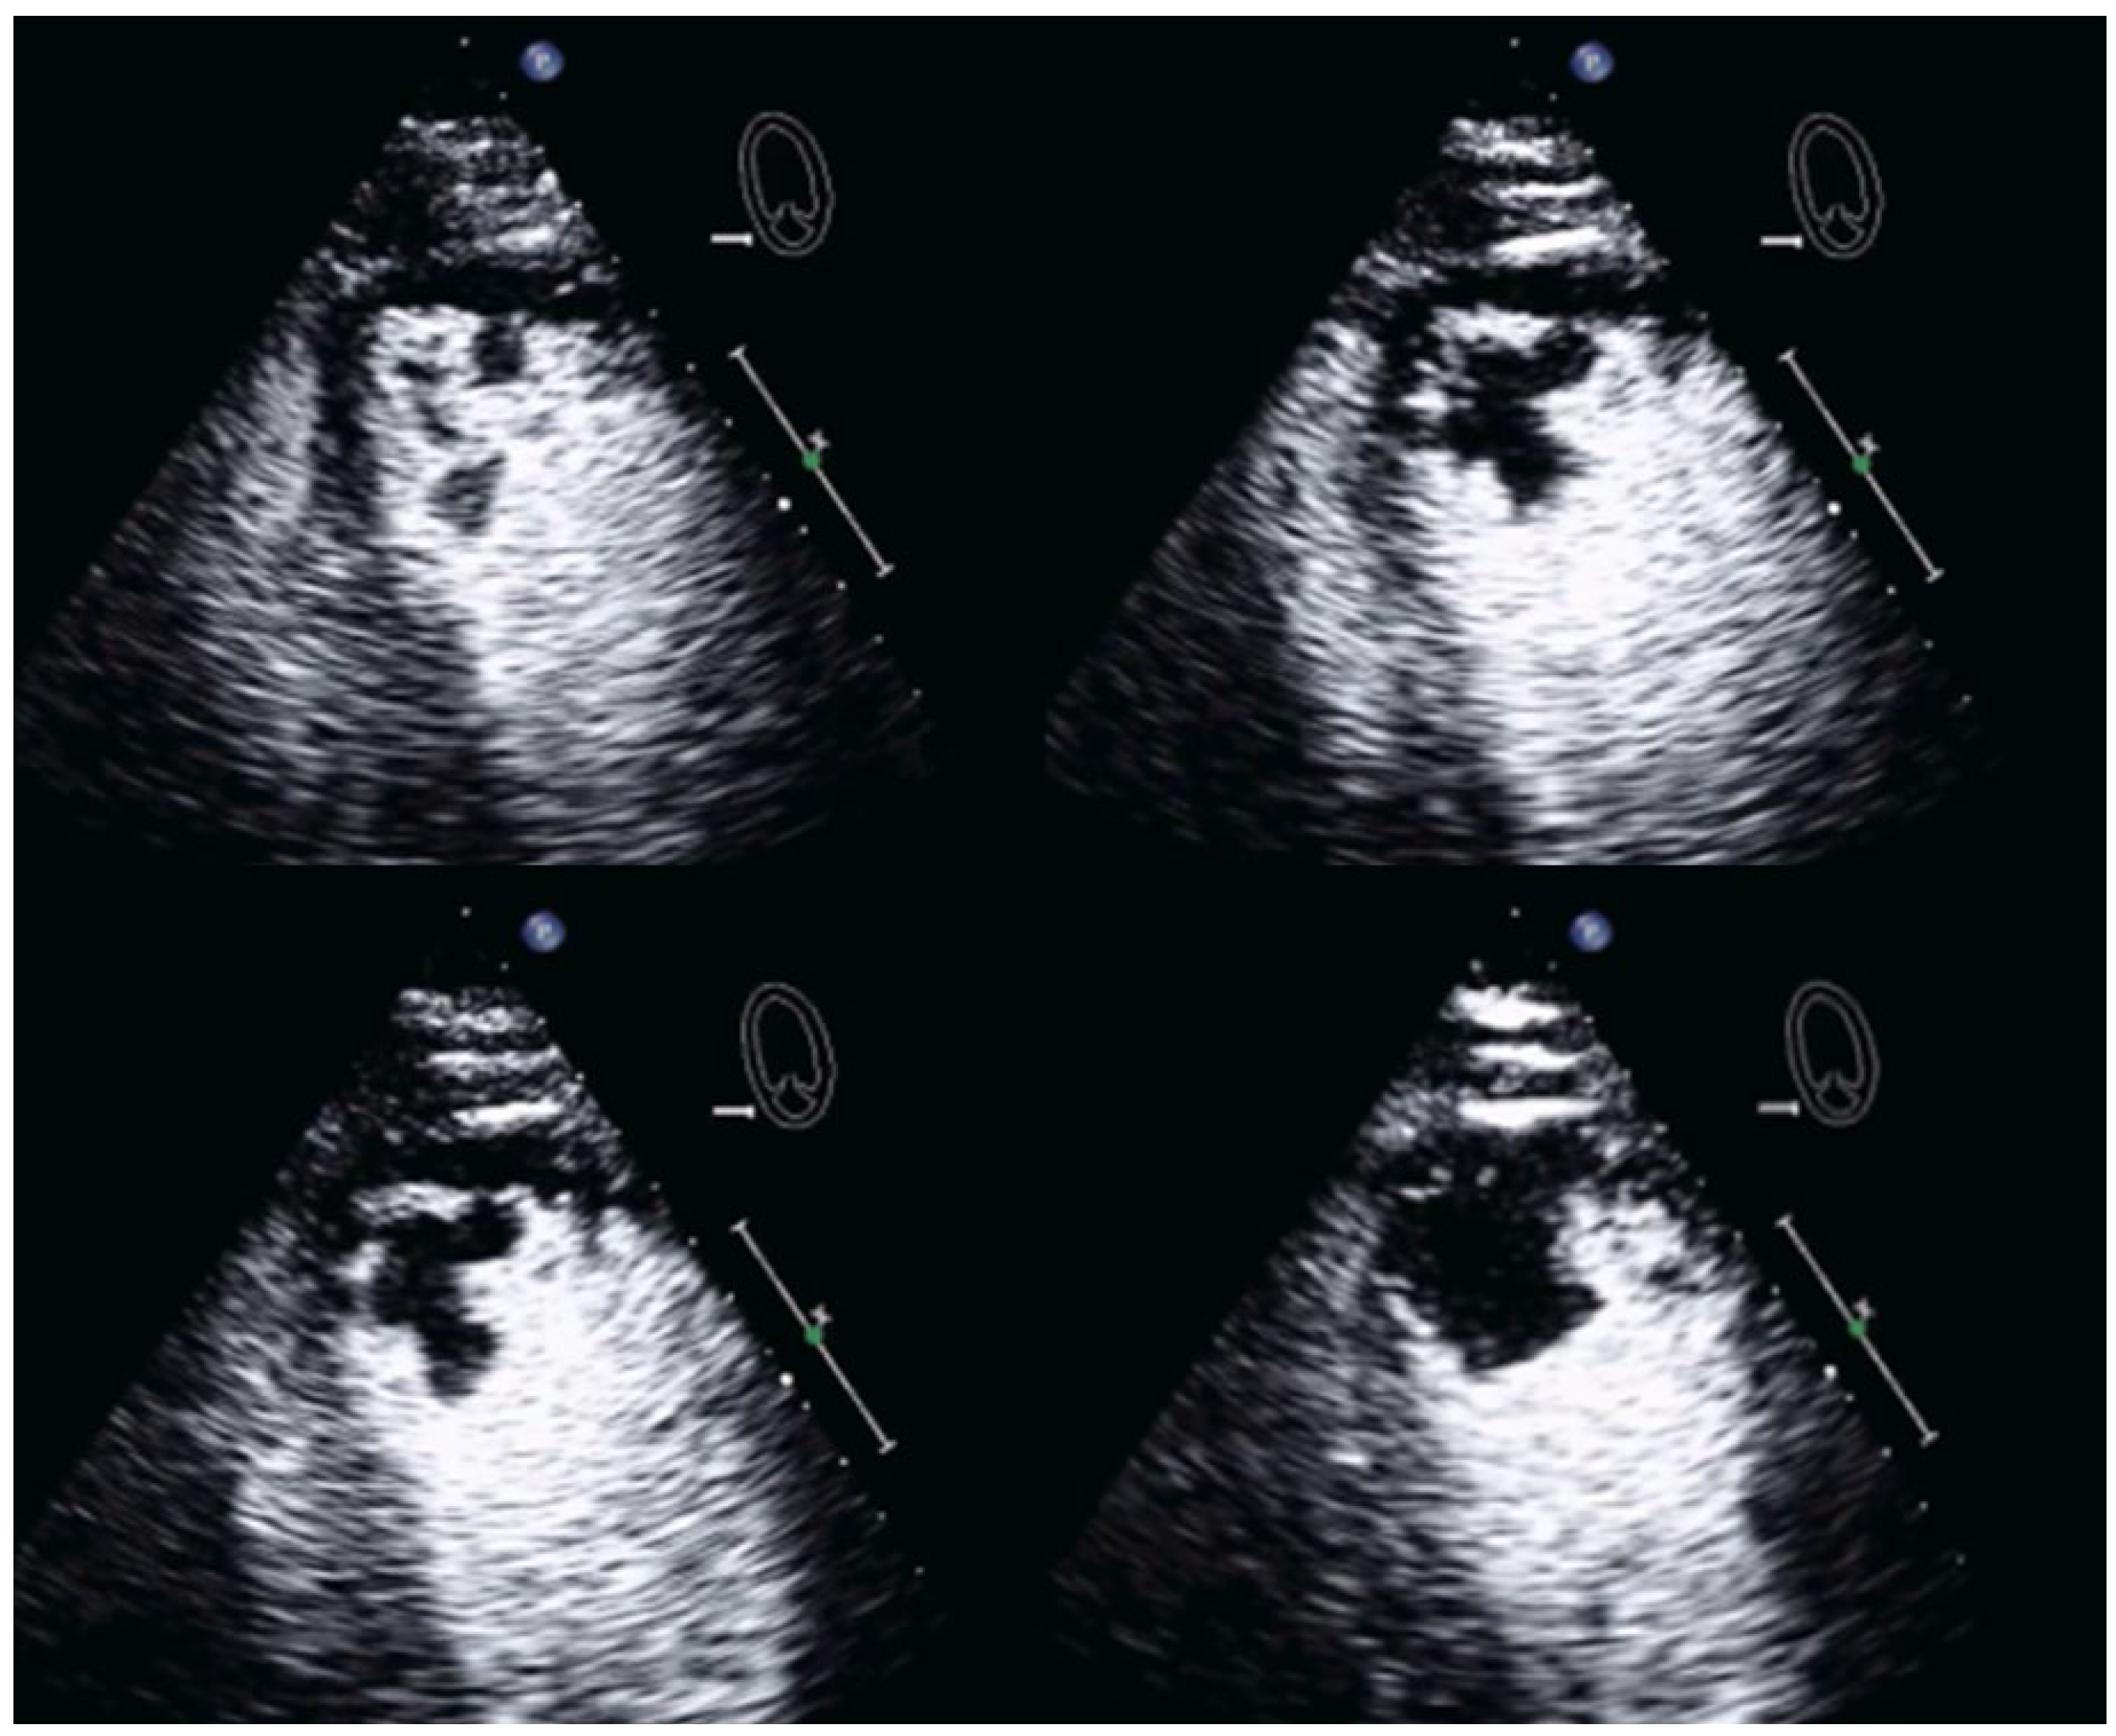

| Imaging method | Low-MI-contrast-specific imaging, additional intermediate-MI imaging in case of apical aneurysm for assessment of thrombus in the aneurysm |

| Imaging planes | Standard apical views and apical sweeps to assess the aneurysm for thrombi |

| Contrast application | Bolus injections |

| Typical finding | 1. Hourglass/ace-of-spades shape of apical LV cavity 2. Apical myocardium appears dark in late systole due to compression of the intramyocardial vessels 3. Apical aneurysms +/− thrombi in some patients |

| Alternative imaging | MRI useful for scar/fibrosis imaging and display of apical aneurysms CT in patients with contraindication for MRI and UEAs |